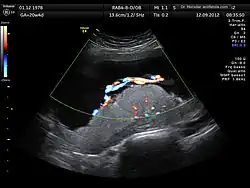

The anomaly scan, also sometimes called the anatomy scan, 20-week ultrasound, or level 2 ultrasound, evaluates anatomic structures of the fetus, placenta, and maternal pelvic organs. This scan is an important and common component of routine prenatal care.[1] The function of the ultrasound is to measure the fetus so that growth abnormalities can be recognized quickly later in pregnancy, to assess for congenital malformations and multiple pregnancies, and to plan method of delivery.[2]

Two-dimensional (2D) is used to evaluate fetal structures, placenta, and amniotic fluid volume. Maternal pelvic organs are also evaluated. Views are obtained using an abdominal ultrasound probe, but a vaginal ultrasound probe may also be used to evaluate for placenta previa and cervical length. Three-dimensional (3D) ultrasound is not recommended for routine use during anomaly scan, but 3D ultrasound may be used to further evaluate suspected abnormalities in specific fetal features.[3]